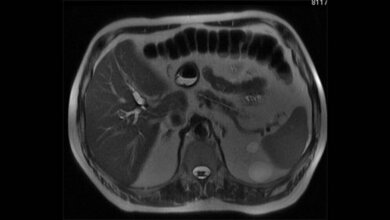

Bei einer Magnetresonanztomografie (MRT) verbessern Kontrastmittel die bildliche Darstellung der Gewebestrukturen. Sie verstärken die Signale in den Blutgefäßen und im Raum zwischen den Zellen, gelangen jedoch nicht ins Zellinnere. Glukose (Traubenzucker) hingegen wird in die Körperzellen aufgenommen und dort abgebaut. Besonders Tumorzellen sind süchtig nach Zucker, um ihren hohen Energiebedarf zu decken. Die Beobachtung der Zucker-Stoffwechselaktivität könnte daher Krebsherde oder sogar besonders aggressiv wachsende Tumorareale identifizieren. Radiologen und Physikern aus dem Deutschen Krebsforschungszentrum ist diese neue Art der Bildgebung nun gelungen.

Die klassische MRT beruht auf der Messung der Signale von Protonen im Wasser. Da der Körper zu über 60 Prozent aus Wasser besteht, entsteht so ein deutliches Bild. Um den viel geringer konzentrierten Traubenzucker sichtbar zu machen, benutzen die DKFZ-Forscher einen Hochfeld-Tomographen mit einer Magnetfeldstärke von 7 Tesla und eine spezielle Methode, um das Glukose-Signal selektiv zu verstärken. Damit lässt sich eine ausreichende Signalstärke erzielen, die es ermöglicht, die Änderungen der Zuckerkonzentration im Hirngewebe nach der Injektion von Glukoselösung sichtbar zu machen.

Der Physiker Patrick Schünke und der Arzt und Physiker Daniel Paech konnten in ihrer aktuellen Arbeit sowohl die Änderung des Glukosesignals von gesunden Hirnarealen als auch die krankhafte Änderung in Hirntumoren beim Menschen beobachten.